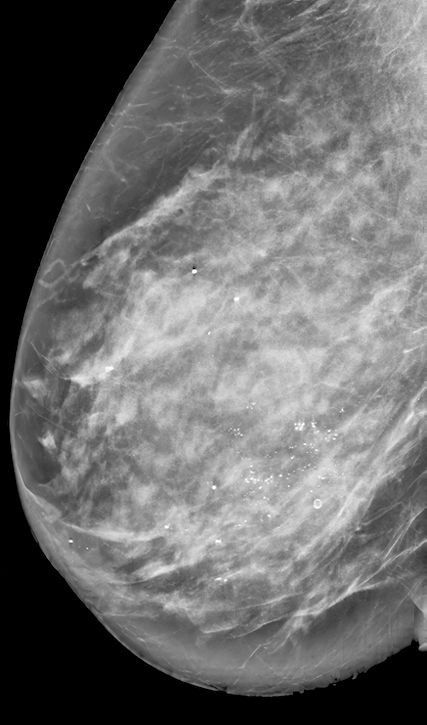

Um auch in Zukunft Patientinnen hinsichtlich der Notwendigkeit einer operativen Therapie des DCIS adäquat beraten zu können, müssen Risikofaktoren für das Vorliegen oder zukünftige Auftreten eines invasiven Karzinoms berücksichtigt werden. Dazu gehören pathologische Faktoren wie «High grade»-DCIS, Comedonekrosen, Hormonrezeptornegativität und HER2-Positivität; patientinnenassoziierte Faktoren wie jüngeres Alter oder erhöhte familiäre Belastung hinsichtlich Mammakarzinom sowie klinische Faktoren wie grössere Läsion (Abb. 3) und Vorhandensein einer assoziierten Raumforderung.19